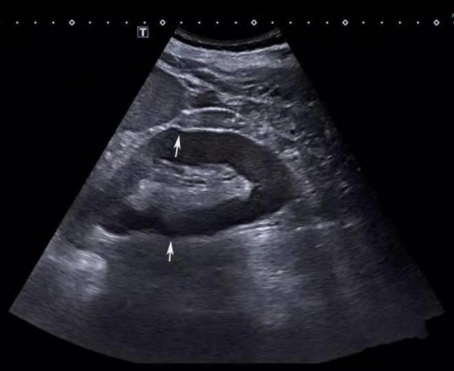

由于脾脏实质与肾脏周围脂肪囊的声速差别,导致肾脏的上半部向前、下半部分向后移位,使肾脏呈现为台阶状扭曲。

由上述声像图得知:脂肪内声速低于1540m/s,声像图上其后方的组织会向深方移位,软骨内声速远高于1540m/s,声像图上其后方的组织会向前方移位。